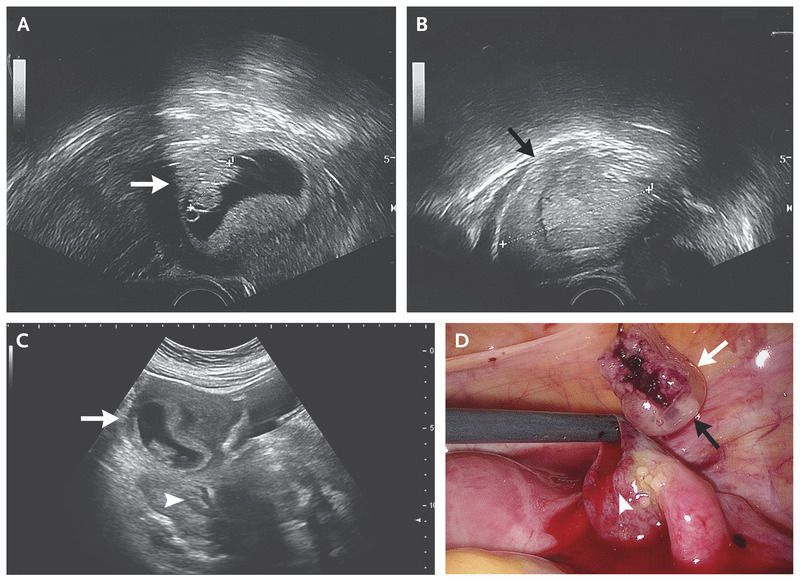

A 34-year-old woman with a history of appendectomy presented to the emergency department after 45 minutes of acute abdominal pain. Her last menstrual period was 9 weeks before presentation, and a normally conceived intrauterine pregnancy (8 weeks of gestation) had been diagnosed by her gynecologist by means of ultrasonography (Panel A, arrow). On examination, she had hypotension, tachycardia, and appreciable tenderness in the right lower abdomen. Transvaginal ultrasonography revealed a 4-cm-by-4-cm right adnexal mass (Panel B, arrow) and intrauterine pregnancy (Panel C, arrow), as well as free fluid in the peritoneal cavity (Panel C, arrowhead), which caused concern about an ectopic pregnancy. An urgent laparoscopy was performed. On laparoscopy (Panel D), a ruptured ectopic pregnancy was seen in the right fallopian tube (arrowhead), and an intact gestational sac (white arrow) and embryo (black arrow) were also seen. Large hemoperitoneum was present, with active bleeding from the ruptured site in the fallopian tube. A salpingectomy was performed. Heterotopic pregnancy is the rare occurrence of a simultaneous intrauterine and extrauterine pregnancy. The incidence of heterotopic pregnancy in natural conception is estimated to be 1 in 30,000 pregnancies. In this case, the intrauterine pregnancy remained intact, and a healthy girl was delivered at term.